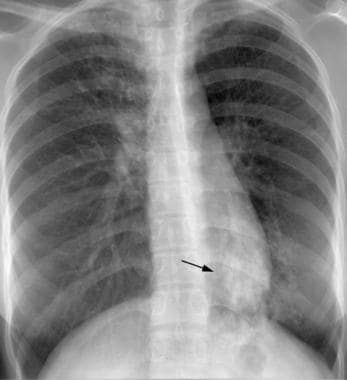

- RTG Klatki Piersiowej: Jednym z najczęściej stosowanych metod obrazowych do diagnozowania gruźlicy pierwotnej jest rentgen klatki piersiowej, który może pokazać obecność nacieków, cieni czy innych zmian charakterystycznych dla gruźlicy.

- Tomografia Komputerowa (CT): W niektórych przypadkach, tomografia komputerowa może być wykonana w celu dokładniejszej oceny zmian w płucach oraz ewentualnego rozprzestrzenienia się gruźlicy do innych tkanek.